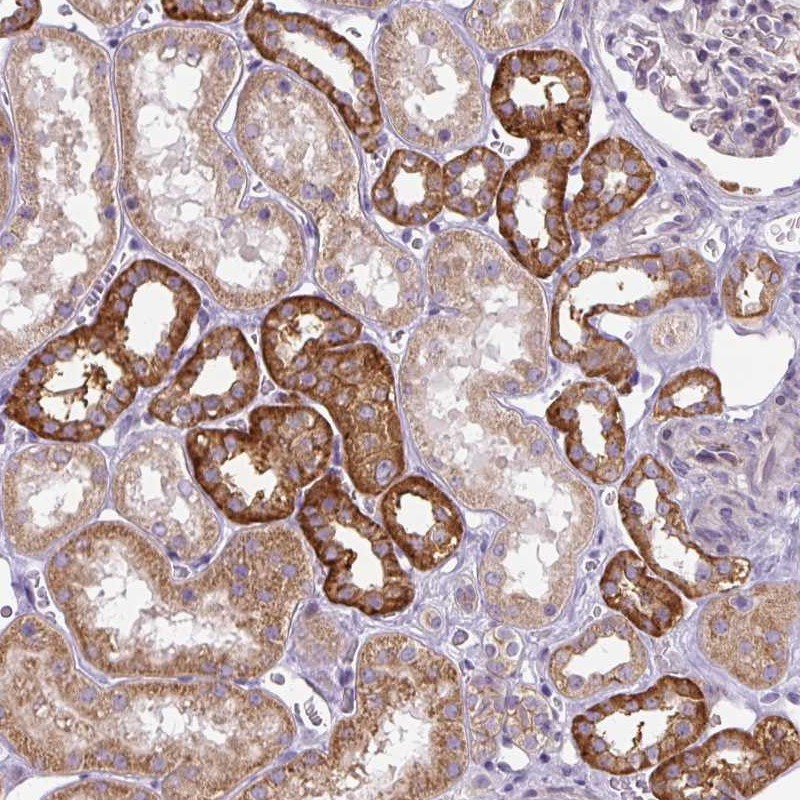

Immunohistochemical staining of human kidney shows strong cytoplasmic positivity in cells in tubules.